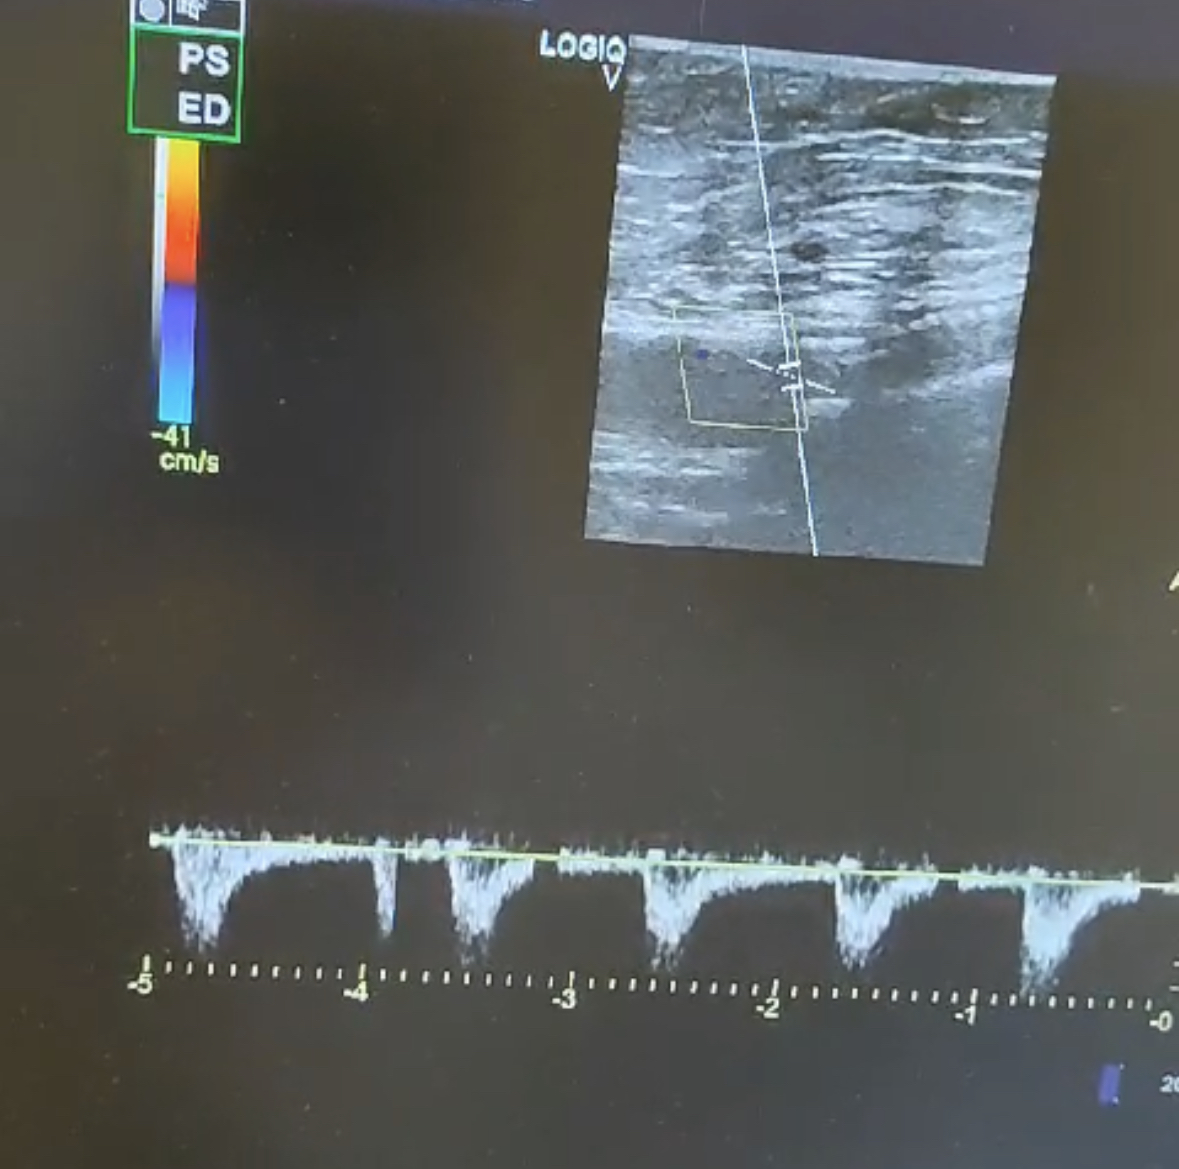

El paciente relata dolor gemelar y aumento de claudicación intermitente. Se realiza ecografía a pie de cama donde se observa trombosis del stent de toda la femoral superficial.

Durante la ecografía se observa sten de la femoral superficial ocluido, observándose flujo en la zona previa al stent y sin observarse flujo sanguíneo en el stent.